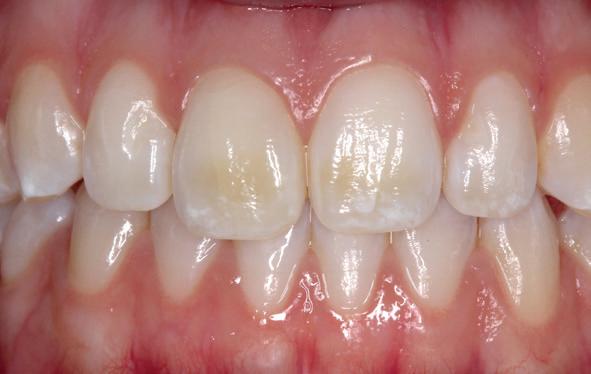

Implantologische behandelingen in het esthetische front vragen meer dan technische vaardigheid alleen. Ze vragen om overzicht, timing, vertrouwen en een team dat als vanzelf samenwerkt onder druk. Juist bij complexe casussen, waarin angst, infectie en hoge esthetische verwachtingen samenkomen, wordt zichtbaar hoe bepalend de rol van de tandartsassistent is.

Deze casus beschrijft een uitgebreide immediate implantaatbehandeling bij een patiënt die door meerdere collega’s werd geweigerd. Niet omdat de mogelijkheden ontbraken, maar omdat de complexiteit vroeg om een perfect afgestemde samenwerking. Het verhaal laat zien hoe de assistent in zo’n traject veel meer is dan een uitvoerende kracht of “mal”, maar een dynamische surgical guide die het proces mede stuurt, bewaakt en mogelijk maakt.De patiënt: wanneer alles samenkomt

Na het klinische onderzoek volgde het röntgenologisch traject. De CBCT liet precies zien wat we al vreesden: een front waarin het bot onregelmatig was, duidelijke radiolucenties rond de pijlers en een infectiegebied dat zich onder vrijwel de gehele brug had verspreid. Tegelijkertijd was er ook potentie. Net voldoende botstructuur om immediate implantaatplaatsing te overwegen, mits alles perfect gepland zou worden.